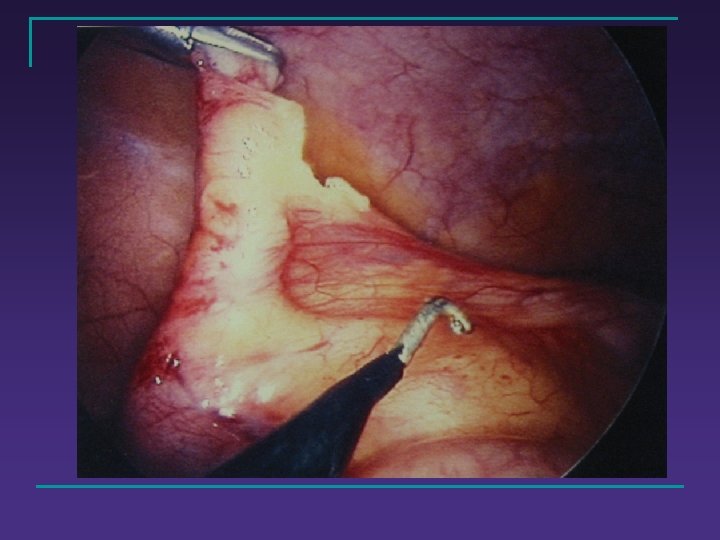

Traitement chirurgical n Appendicectomie q q par voie de Mac Burney cœlioscopique n n Trans-ombilicale / 3 trocarts Drainage = 0